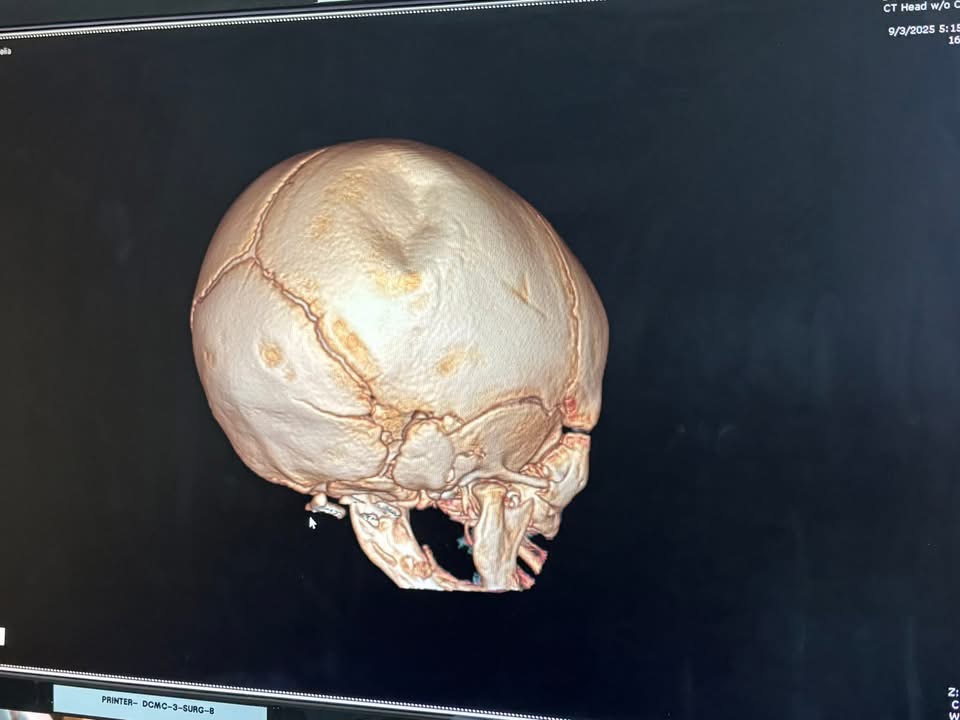

Amelia, a beautiful, innocent baby girl, was brutally and senselessly hurt at the hands of her own father over the course of her extremely short life. She was rushed to the hospital where doctors discovered a fractured skull, requiring emergency surgery. Further scans revealed the heartbreaking truth: multiple other fractures throughout her tiny, defenseless body, injuries no child should ever suffer.